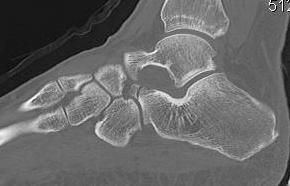

Fracture lateral process of talus